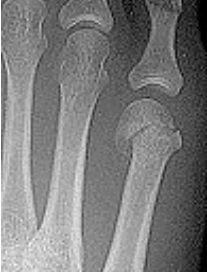

What disease is this? What indicates this? | Tophaceous gout. Soft tissue swelling surrounding the index finger PIPJ, with associated erosion and bone resorption |